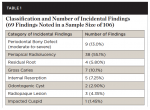

The incidental findings reported were divided into subcategories that included the presence of a periodontal bony defect, periapical radiolucency, residual root, gross caries, internal resorption, odontogenic cyst, radiopaque lesion, and impacted cuspid.The most frequent incidental findings were in the form of periapical radiolucencies (38 instances noted) (Figure 2). As can be seen in Figure 3, which shows the frequency of all incidental findings within each age group, 63 of the 69 incidental findings noted in this study were found in patients aged 41 years or older. Table 1 denotes both the category and number of incidental findings.